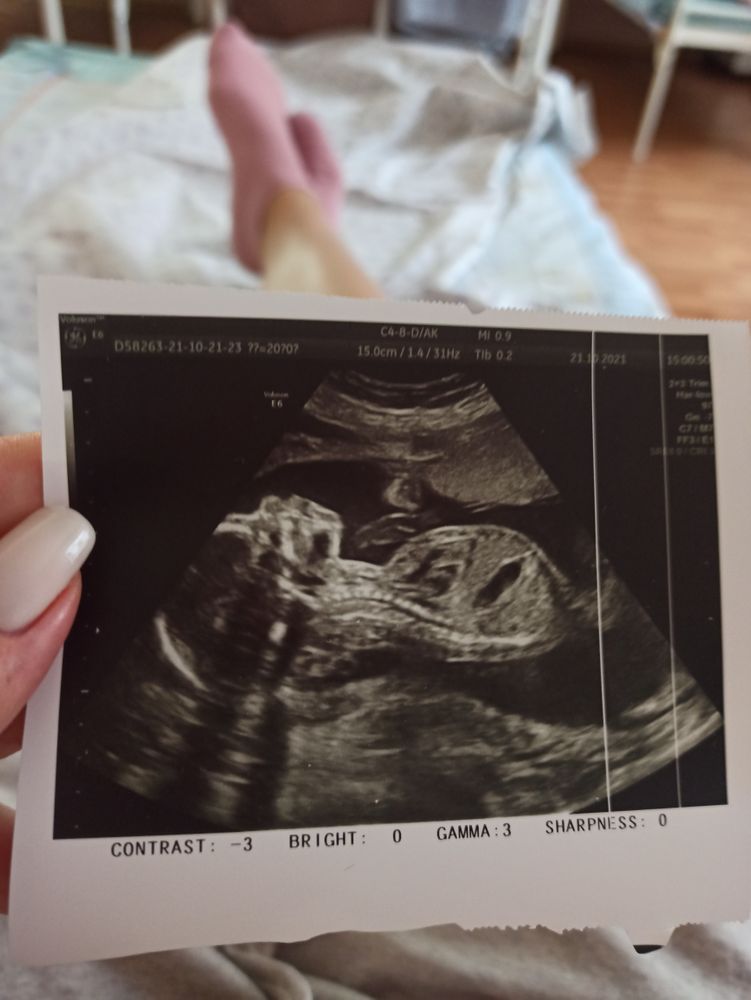

Всё у нас хорошо ❤️

Лежит загорает барышня 🥰

Ну что там за пупсик такой сладкий живет😍😍😍 ттт на вас! Какая ты позитивная! Очень рада, что все хорошо, но раз такая особенность, лучше, как говорится, перебдеть🙌